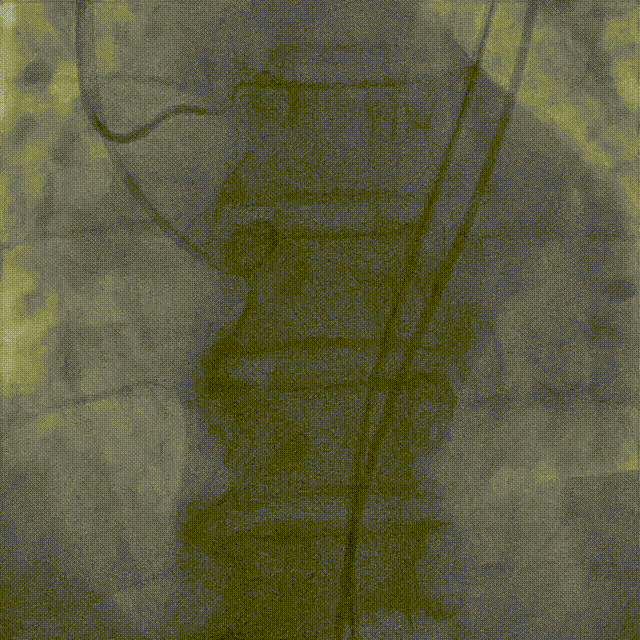

谷兴华教授 山东大学齐鲁医院 锚定终身获益,重视首次干预选择:心脏瓣膜病介入中心成立2年多来,中心核心目标始终保证在解决即刻病症的基础上,护航患者的全生命周期健康管理。 摆在眼前的实际是日益年轻化的患者群体,这意味着我们从手术伊始,就必须将患者未来数十年的生活质量和再次干预风险纳入核心考量,主动规划长远的健康路径。此次患者选择更具耐久的新型干瓣技术,力求减少患者未来再次干预的风险。同时,通过“TAVR+PCI一站式手术”这样的团队协作模式,系统性地处理多重心血管问题,避免分次手术的负担与风险,这正是我们中心一直秉持的“心脏瓣膜病全生命周期管理”理念的实践。让我们一起探索从“治已病”真正迈向“管长远”,让更多的患者获益! 病例特点速览 本次救治的患者,病情呈现“基础病交织、多病变叠加、锚定风险高”三大核心特征。患者为65岁,女性,病变特点TypeI型二叶瓣、轻度钙化,锚定风险大;同时患有冠状动脉粥样硬化性心脏病、慢阻肺(COPD);既往有长期吸烟饮酒史、脑梗死病史、高血压病史、乙肝小三阳病史及腹股沟疝修补手术史,患者STS评分9.32%,外科手术高危,经齐鲁医院瓣膜中心团队评估认为:局麻下“一站式TAVR+PCI”为最优治疗方案,结合患者较年轻,可选择具有长期耐久性的干瓣。 患者病史 主诉:活动后胸闷、憋喘余,加重20余天 既往史:30年前确诊乙肝小三阳,否认其他传染病史;有右腹股沟疝修补手术史,高血压病史,近期规律服药控制。 现病史:患者1年前出现活动后胸闷、憋喘,休息可缓解,为进一步诊治。2月前因“突发意识模糊、口齿不清”于当地医院入院,诊断为“急性脑梗死”,予以微创介入取栓治疗,恢复可,未遗留后遗症。20天前于当地医院再次入院行脑血管支架植入术,术后出现胸闷、憋喘,伴大汗,行心脏超声提示主动脉瓣重度狭窄,并行冠脉造影检查,予以药物治疗。10天前就诊于我院复查心脏超声提示二叶式主动脉瓣,主动脉瓣狭窄(重度)并反流(轻度)。患者现仍感胸闷,双上臂疼痛不适,咳嗽咳痰,日常活动受限。为行进一步治疗就诊于我院,门诊以“主动脉瓣狭窄、冠状动脉粥样硬化性心脏病”收入院; 个人史:吸烟50年,饮酒50年; 体格检查:体温:36℃,脉搏:67次/分,呼吸:18次/分,血压:143/76mmHg; 术前超声提示: 二叶式主动脉瓣主动脉瓣狭窄(重度)并反流(轻度);升主动脉扩张、左心扩大三尖瓣反流(少量);左室充盈异常;CW测最大压差86mmHg,平均压差43mmHg,最大血流速度463cm/s,连续方程法估测主动脉瓣口面积0.78cm² 术前CT评估 Type1型二叶瓣,轻度钙化、左右融合,主动脉瓣环径25.3mm,LVOT直径25.5mm,鱼嘴空间约26.6mm,主要靠瓣环锚定。窦部空间大、左右融合,VTC空间足够,无冠脉风险 ;左室内径正常,主动脉瓣环水平夹角49.6°。外周双侧入路内径可,髂外动脉存在散在钙化、双侧入路能够支持20F大鞘通过,右股低分叉,主动脉弓距弓角可。 个性化手术策略:局麻一站式方案+创新瓣膜精准适配 入路选择:主入路:右侧股动脉(右股分叉上方1cm处穿刺);辅入路:左侧股动脉;器械:20F大鞘; 手术流程规划:局麻下行同期一站式TAVR+PCI,植入ProStyle A®预装干瓣; 瓣膜选型与预处理:瓣膜型号:ProStyle A® AV32;不预扩; 定位与释放方案:初始定位:瓣上3mm处释放,瓣膜自然下滑至工作位,最终目标“0-瓣下5mm位”。 手术过程:局麻一站式操作+创新瓣膜植入,无缝衔接 手术团队按预设方案稳步推进,实现TAVR、PCI与ProStyle A®干瓣植入的无缝衔接: 1.术前准备:完成影像评估、血管通路建立,确认ProStyle A® AV32瓣膜状态; 2.PCI治疗:通过主入路完成左冠造影,前降支、对角支明显狭窄,精准植入两枚支架,恢复冠脉血供; 左冠造影,前降支、对角支病变 PCI后造影,病变血管充盈良好 3.主动脉根部造影:确认主动脉根部解剖结构,并精准跨瓣; 主动脉根部造影 精准跨瓣 4.干瓣植入:将瓣膜输送过弓、过瓣,并精准定位; 输送系统柔顺过弓 精准定位 5.术中评估:释放瓣膜至工作状态,再次造影评估,位置满意,完全释放瓣膜; 工作位评估 32号瓣膜稳定脱钩 6.释放后造影:可见瓣膜位置满意、形态良好,无明显瓣周漏。 最终造影,位置形态良好,无瓣周漏 术后超声探查:位置(瓣下4mm)、形态良好,无瓣周漏,PGmean=10mmHg。 此次手术的成功,体现了山东大学齐鲁医院心脏瓣膜病介入中心秉承的“心脏瓣膜病全生命周期管理”的理念和团队协作的临床能力。面对低龄高风险复杂病例,团队通过术前充分评估、术中精细操作,结合具有长期耐久性的干瓣技术,以一站式方案改善患者症状、提高生活质量并延长寿命,为类似病例的诊疗提供宝贵经验。 专家简介 谷兴华 山东大学齐鲁医院(点击查看专家详细简历)